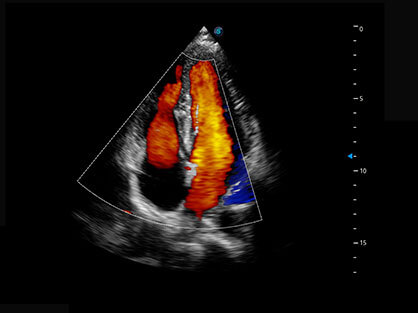

• Wi-Flow

通过对组织运动信息、血流信号及背景噪声进行准确智能的阈值判定,高效提取出微弱血流信号,获得高灵敏度和空间分辨率的血流图像,为临床提供更加真实和丰富的诊断信息。